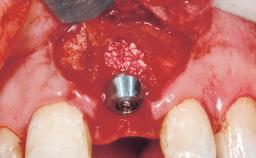

A 29-year-old female patient presented for treatment to replace the upper left central incisor tooth with an implant- supported restoration. The tooth had been intermittently symptomatic for the previous 12 months. The tooth had originally suffered trauma about 15 years previously. Several endodontic treatments had been performed, including an apicectomy procedure to retain the tooth. The patient was healthy and a non-smoker. She had reasonable expectations in regard to esthetic outcomes and the risk of marginal tissue recession following treatment. At medium smile, the gingival margins of the upper teeth were visible, with a display of 3 to 4 mm of the gingival margins. Gingival recession of tooth 21 and a discrepancy in the gingival levels between teeth 11 and 21 was observable during normal speech and smile.

Placement Protocol Immediate implant placement

Tooth Site Maxillary incisor or canine

Socket Morphology Single-root socket

Socket Integrity Damage to one or more bone walls

Bone Volume Damage to one or more socket walls